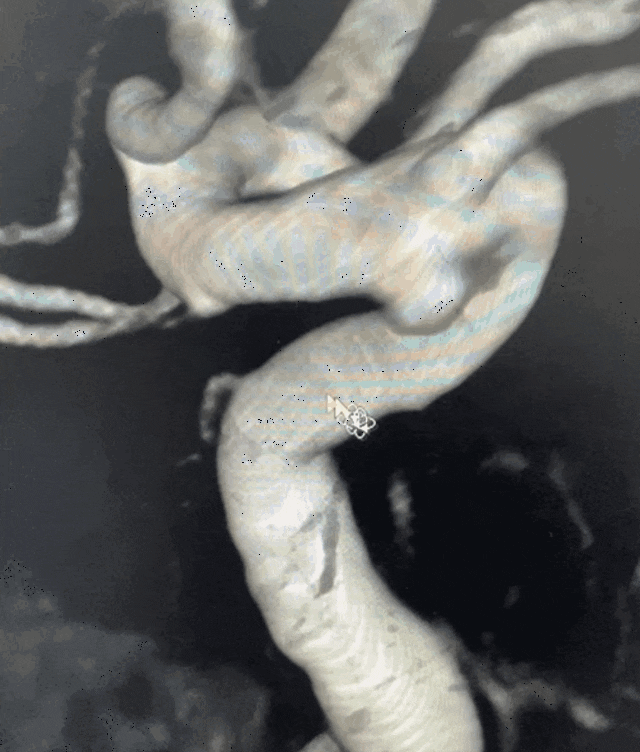

密网支架覆盖长度

▲术前3D测量

经检查,张某左侧颈内动脉C6段可见异常隆起,大小约为:2.6mm×2.1mm×2.3mm,考虑为动脉瘤,神经外科医疗团队经过多学科会诊和论证,决定为其实施目前国内外先进的血流导向装置进行介入治疗。